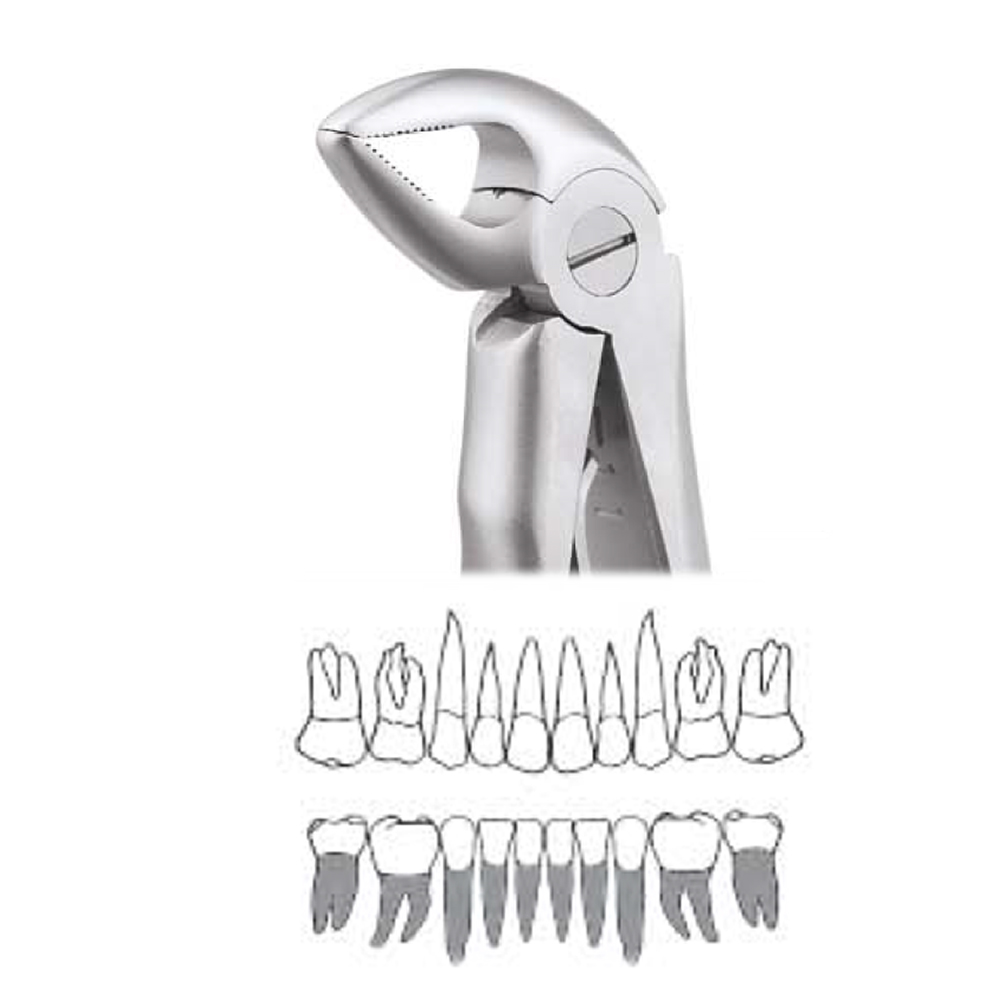

Pedo Extraction Forceps: These specialized forceps are designed to extract deciduous (baby) teeth gently. They have smaller, anatomically adapted beaks that fit comfortably around the smaller roots of baby teeth, reducing the risk of trauma during extraction. The handles are designed for easy grip and better control, ensuring a safe and efficient extraction process.

Pedo American Forceps: These forceps are designed to grip and extract deciduous teeth that are mobile or need removal. They have unique beak designs that cater to the varying shapes and sizes of baby teeth, providing a secure hold for extraction while minimizing any discomfort for the child.